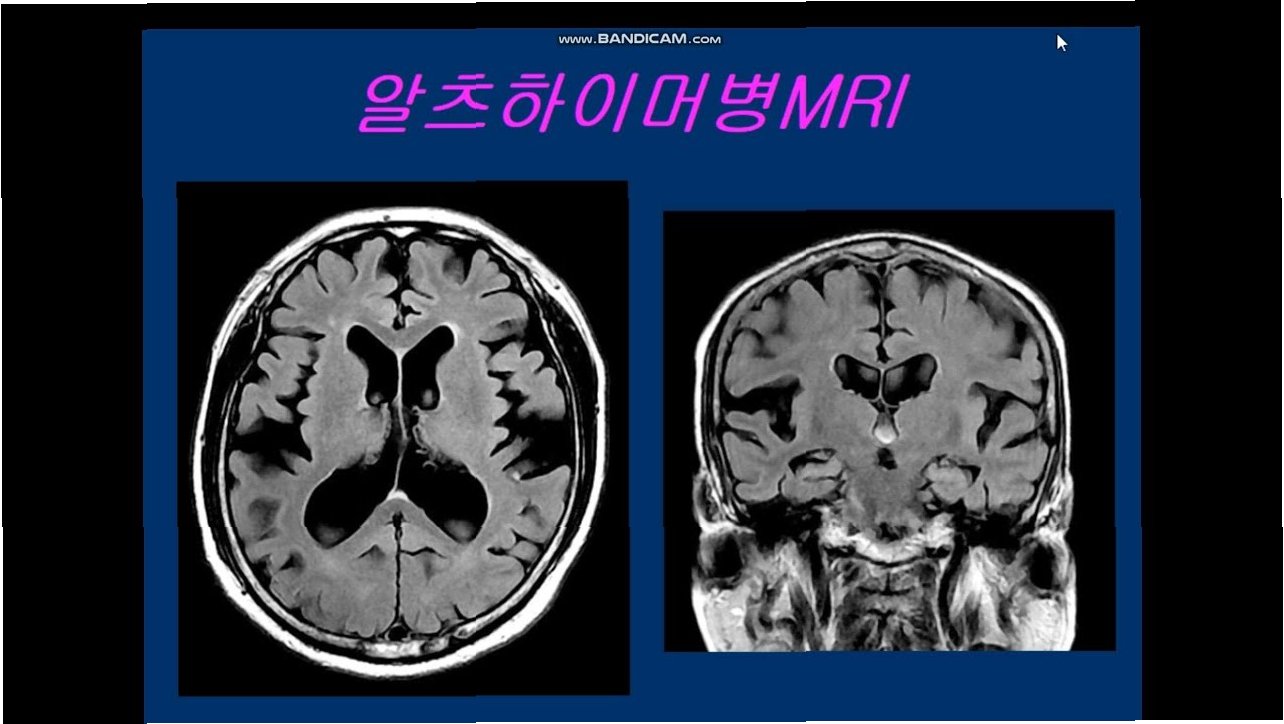

알츠하이머병은 기억력 감퇴, 인지 기능 저하를 특징으로 하는 퇴행성 뇌 질환입니다. 전 세계적으로 수백만 명의 사람들이 이 질병으로 고통받고 있으며, 그 수는 계속 증가하는 추세입니다. 하지만 절망할 필요는 없습니다. 알츠하이머병은 치료와 예방을 통해 관리할 수 있으며, 삶의 질을 개선할 수 있는 방법들이 존재합니다. 이 글에서는 알츠하이머병의 치료와 예방에 대해 심층적으로 다루며, 독자들이 뇌 건강을 지키는 데 필요한 정보와 실질적인 조언을 제공합니다.